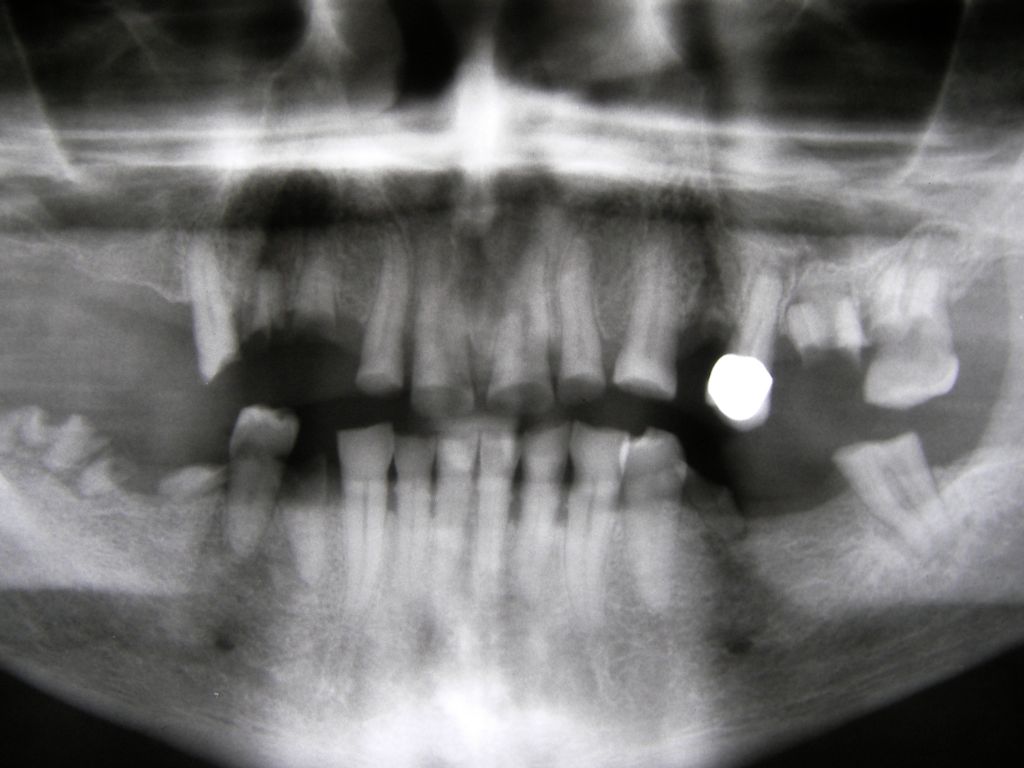

Besonderen Spaß macht mir großer, kombiniert festsitzend-herausnehmbarer Zahnersatz (sogenannter Kombi-Ersatz), auch mit Implantaten, weil er interessante Herausforderungen an den Behandler stellt. Diese Behandlungen sind oft langwierig, weil ein Behandlungsschritt auf dem anderen aufbaut: Häufig Parodontaltherapie, Wurzelkanalbehandlungen, Füllungstherapie, Implantate, erst am Ende Zahnersatz. Ob der Fall zur Zufriedenheit des Patienten gelöst werden konnte, stellt sich dann oft erst nach Monaten heraus. | |

Hier ein einfacher Fall, bei dem keine besondere Vorbehandlung notwendig war. Der Patient, 58jährig, suchte die Praxis erstmals im September 2005 auf. Es erfolgten mehrere prothetische Planungen, der Gutachter des "Medizinischen Dienstes der Krankenkassen" (MDK) wurde noch von der Krankenkasse in Anspruch genommen, was heute bei größeren Planungen der Regelfall geworden ist. Umgesetzt wurde dann eine für einen solch großen Fall preisgünstige Lösung von 6434 Euro Gesamtkosten (4264 Laborkosten, 2170 Honorar). Die Krankenkasse übernahm als Festzuschuß 3843 , für den Patienten verblieben 2591. Im Januar 2006 ging es dann endlich los - zunächst allerdings beim Kieferchirurgen, weil wegen einer erhöhten, medikamentös bedingten Blutungsneigung es sicherer erschien, einige Zahnentfernungen von diesem durchführen zu lassen. Ausgangsbilder: |